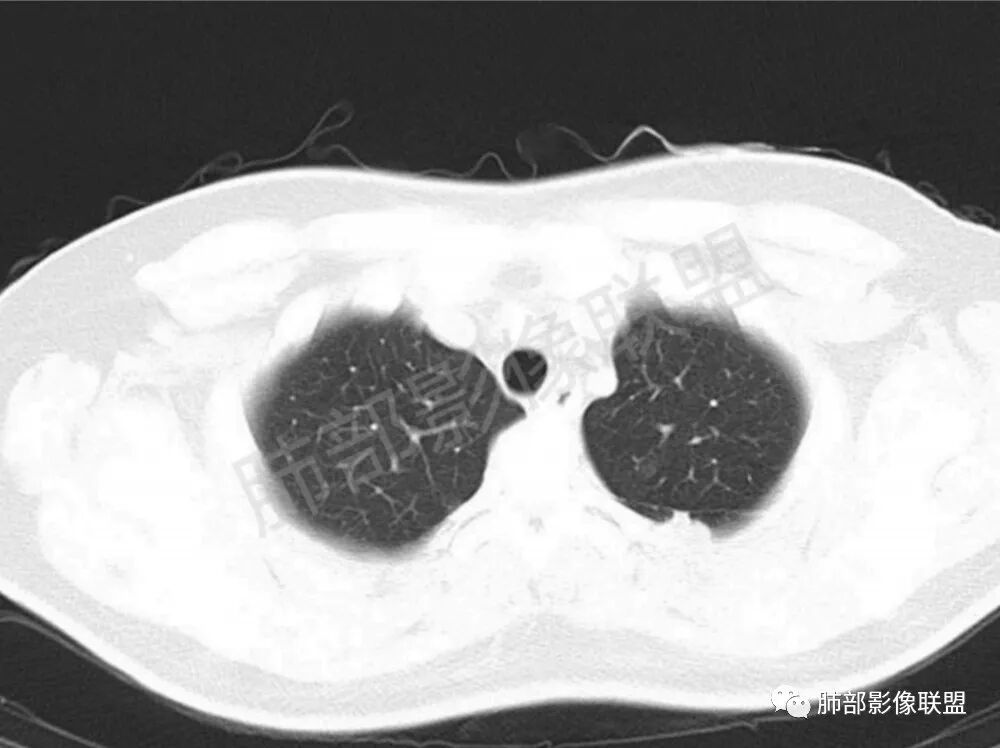

男性,22岁,HIV病史,症状半年,双肺多发大小不等结节影,边缘光滑,密度均匀,以胸膜下分布为主,部分与胸膜相连,胸膜下脂肪间隙可见,病灶近段支气管走行病灶内,远端似有堵塞,无增强图像,考虑隐球菌,鉴别:淋巴瘤,GPA

双肺多发结节影,膨隆,边缘光滑,圆顿,沿支气管血管束分布为主,部分贴胸膜,部分见空洞,空气支气管征

两肺多发结节性,大部分位于胸膜下,部分结节周围可见晕征。局部结节内可见扩张的支气管,纵隔淋巴结大,脾大,22岁男,HIV阳性,常规先考虑隐球菌。鉴别淋巴瘤,结核,马儿。

男,22,半年前咳嗽伴少痰,查HIV阳性,痰查TB阳性,既往有肺部斑片影伴空洞、纵隔淋巴结肿大、脾大。SCC、CA50、CA199、FER增高,此次胸部CT:两肺多发结节影,部分沿血管束分布,部分贴胸膜下,大小不一,密度不一,部分较散、边缘模糊,部分较实、圆钝、周围模糊晕,部分结节有支气管进入穿行自然,部分结节有血管分支自如通过。考虑HI∨相关淋巴增殖类病变,淋巴瘤?LYG?鉴别PC、TB。

1.双肺多发大小不一结节,外围为主,边界尚清,部分周围似有GGO

2.类圆形,部分与胸膜相连,糊墙

3.支气管通畅或近端堵塞